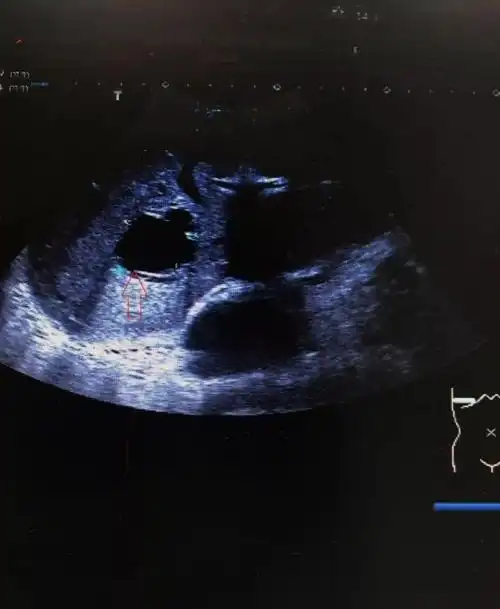

各式各样的肝囊肿,你都见过吗?

肝囊肿超声诊断

一文读懂肝囊肿的超声诊断诊断要点